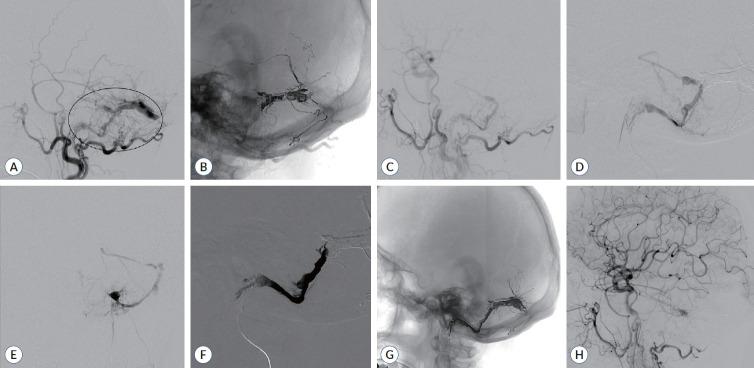

利用咽升动脉进行颅部硬脑膜动静脉瘘的Onyx栓塞术:一项回顾性分析

This retrospective study evaluates our experience with transarterial embolization (TAE) of dural arteriovenous fistulas (dAVFs) using the ascending pharyngeal artery (APA), considering its selective application as a route for the treatment.

We performed a retrospective analysis of medical records and radiologic data of all patients who underwent TAE through the APA at our institution from January 2009 to April 2021.

We identified 305 patients with cranial dAVFs treated endovascularly at our center, focusing on 11 cases (3.6%) where the APA was used for Onyx embolization. Of the 11 dAVFs, five (45%) were completely occluded, three (27%) showed residual shunt but cortical venous reflux disappeared, and three (27%) showed decreased shunt flow but persistent cortical venous reflux. Cranial nerve palsy occurred in two of the cases in which TAE was performed with the jugular branch and hypoglossal branch of the neuromeningeal trunk, which partially improved over 4 to 6 months. No new instances of infarction or hemorrhage were noted on subsequent magnetic resonance angiography.

Transarterial Onyx embolization through the APA could be a limited option reserved for cases where embolization using other branches is challenging or carries a high risk of incomplete treatment. While embolizing through the jugular and hypoglossal branches of the APA neuromeningeal trunk requires greater caution, selecting the posterior meningeal artery or pharyngeal trunk appears to be associated with a lower risk. A comprehensive understanding of angiography is crucial for identifying cases suitable for this approach and those with a higher risk of complications.